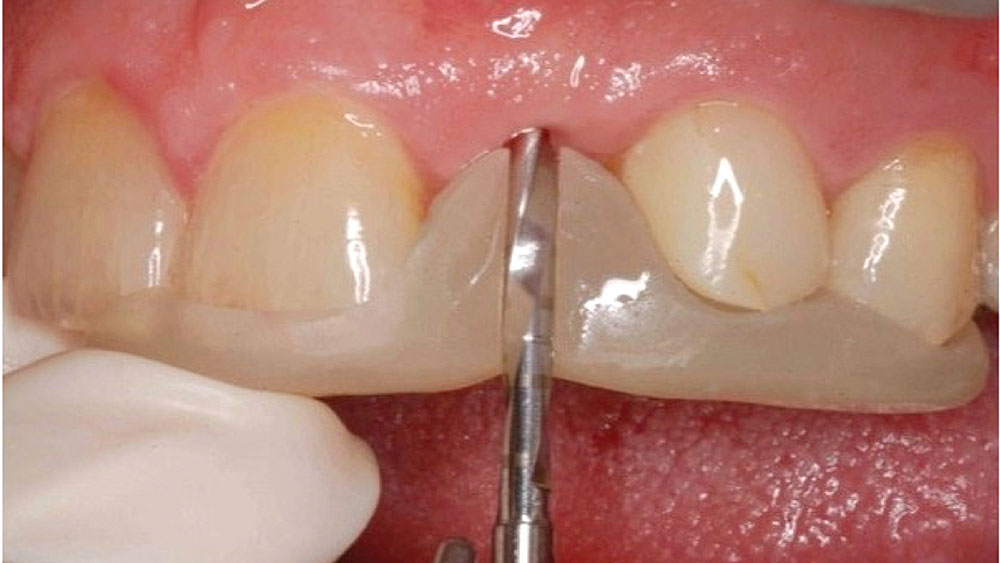

Most patients desire an esthetic result when viewed with a mirror at a 10-inch distance. Placing an implant in a grafted, healed extraction site typically allows for the natural tissue tone and texture patients desire, as well as the keratinized soft tissue needed to fill the embrasures and avoid black triangles around the restoration. Achieving proper apicocoronal implant positioning as described above helps avoid any visible metal at the gum line. It’s also important to choose a ceramic material that blends well with the color, contours and texture of adjacent teeth.

This case is an example of an ideal clinical situation for dentists who are new to placing implants in the esthetic zone. The patient requested treatment for a fractured upper lateral incisor. After extraction, grafting and healing, ample bone and soft tissue were present, and an implant was placed in optimal position for an esthetic result. The screw-retained restoration predictably restored form and function, illustrating the beautiful results that can be achieved by observing simple surgical and prosthetic guidelines.